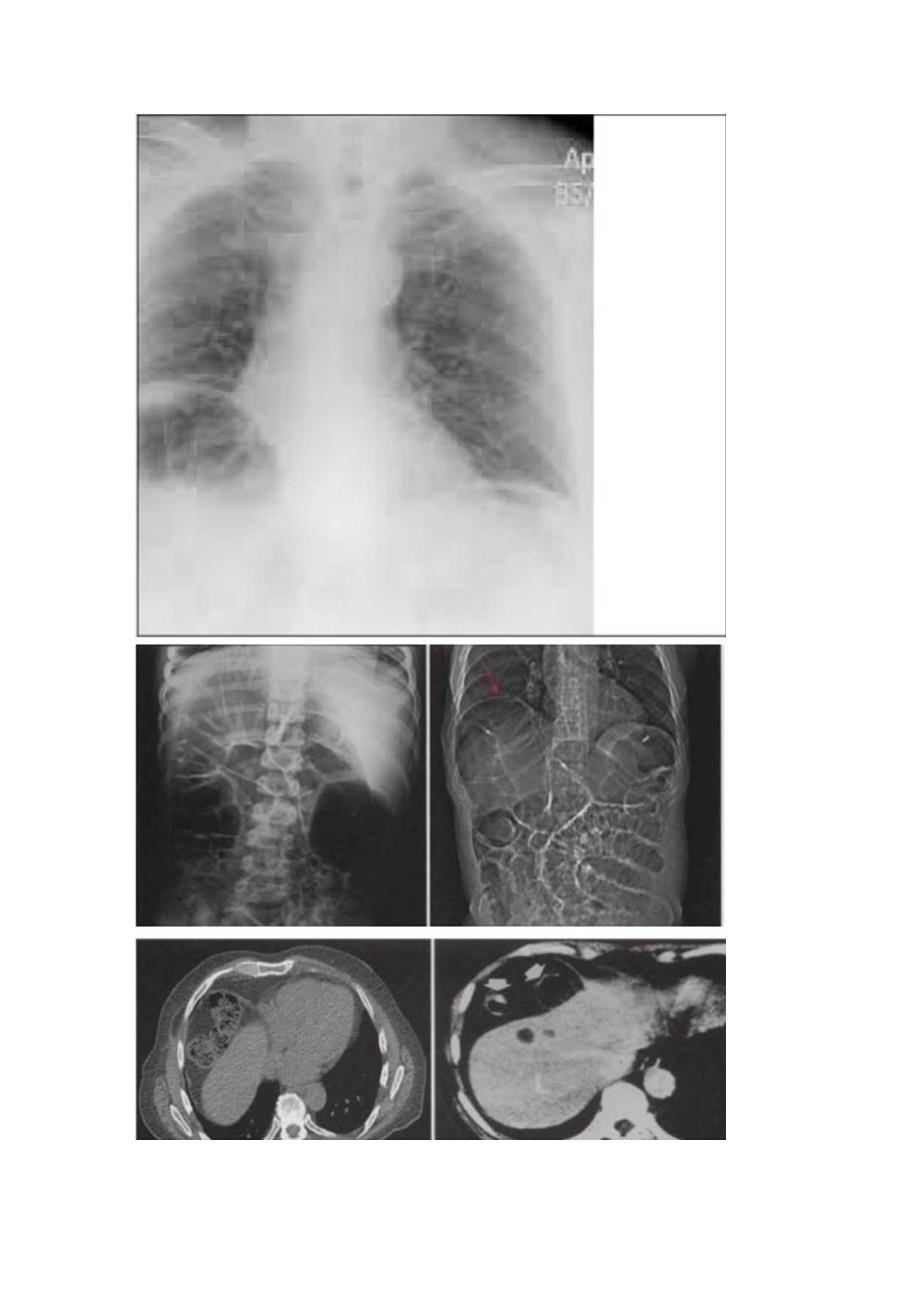

1、临床Chi1.aiditi征病理、临床表现、影像表现、鉴别诊断及典型图像Chi1.aiditi征是指结肠(多为肝曲)由肝前间隙或肝后间隙进入肝与膈之间。在引起腹部或胸部症状时(右季肋部隐痛、腹胀甚至消化道梗阻)称为ChiIaiditi综合征(Chi1.aiditisyndrome),或间位结肠综合征或游走肝综合征。1910年由希腊放射学家DemetriUSChi1.aiditi首次在报道。发表机制:其原因并非结肠本身,肝卜.垂和结肠位置异常是形成本病的基础。肝的韧带过长、薄弱、缺无等发育异常使肝下移,肝膈间隙增宽,以致结肠嵌入其间,形成此病;膈肌的先天薄弱或膈肌麻痹为本病的促发因素:此外在部分

2、肝硬化患者中因肝右叶萎缩明显,肝膈间隙增大也可见此症。国外报道该病的发病率为0.02%0.2%o临床表现:平时常无症状,部分可表现为上腹不适,轻度腹胀,以餐后右上腹最明显。当嵌入的结肠发生梗阻时,常感到上腹突发张痛难忍,并有憋气感及后背放射痛:经数小时至数日症状消失,而且大多于活动后突然消失疾病人群分布。中老年患者,尤其50s60岁多见。男女比例约为4:1。若非恶性肿瘤所致,预后良好治疗。对部分症状较重,并呈进行性、持续性加重,尤其在儿童时期症状严重,影响食欲,妨碍生长发育者,可考虑外科根治性手术治疗,固定肝和结肠,预后较好。症状轻者可不必治疗,经卧床休息,避免在食管中产气等,则大部分自行缓解。影像表现I右膈下袋状气体密度影及环状黏膜皱裳影,随体位改变其位置无变化。若X线平片诊断有疑问,CT可确诊。鉴别诊断:需与消化道穿孔致膈下游离气体相鉴别;前者膈下气体透光区有一光滑边界(肠管壁),可见结肠皱裳,相对应肝表面有局部弧形压迹,改变体位图象改变不大,临床上无急性腹膜炎体征。后者为膈下半月形透光影,肝表面无压迹,体位变动可使膈下透光区改变,临床上多有急性弥漫腹膜炎体征。典型图像